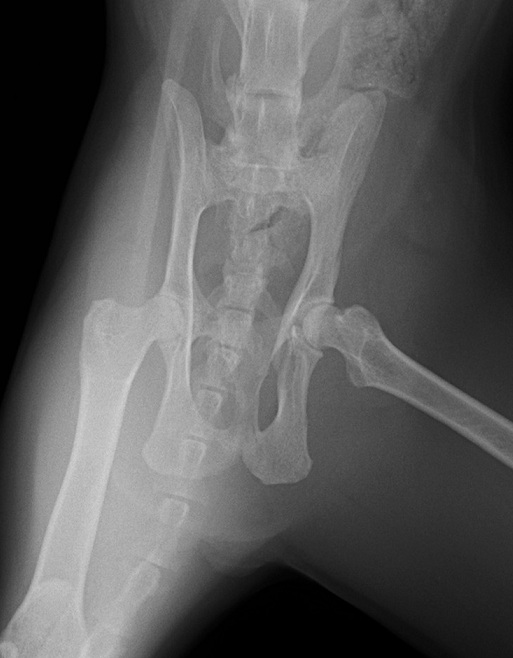

レントゲン検査で、左側の仙腸関節離断と同側の寛骨臼の骨折をしていることがわかりました。 寛骨臼の骨折は坐骨からの斜骨折を伴うもので、人の下顎骨骨折に用いられるMatrix Mandibleというプレートで整復しました。

腹背像

レントゲン検査で、左側の仙腸関節離断と同側の寛骨臼の骨折をしていることがわかりました。 寛骨臼の骨折は坐骨からの斜骨折を伴うもので、人の下顎骨骨折に用いられるMatrix Mandibleというプレートで整復しました。

腹背像